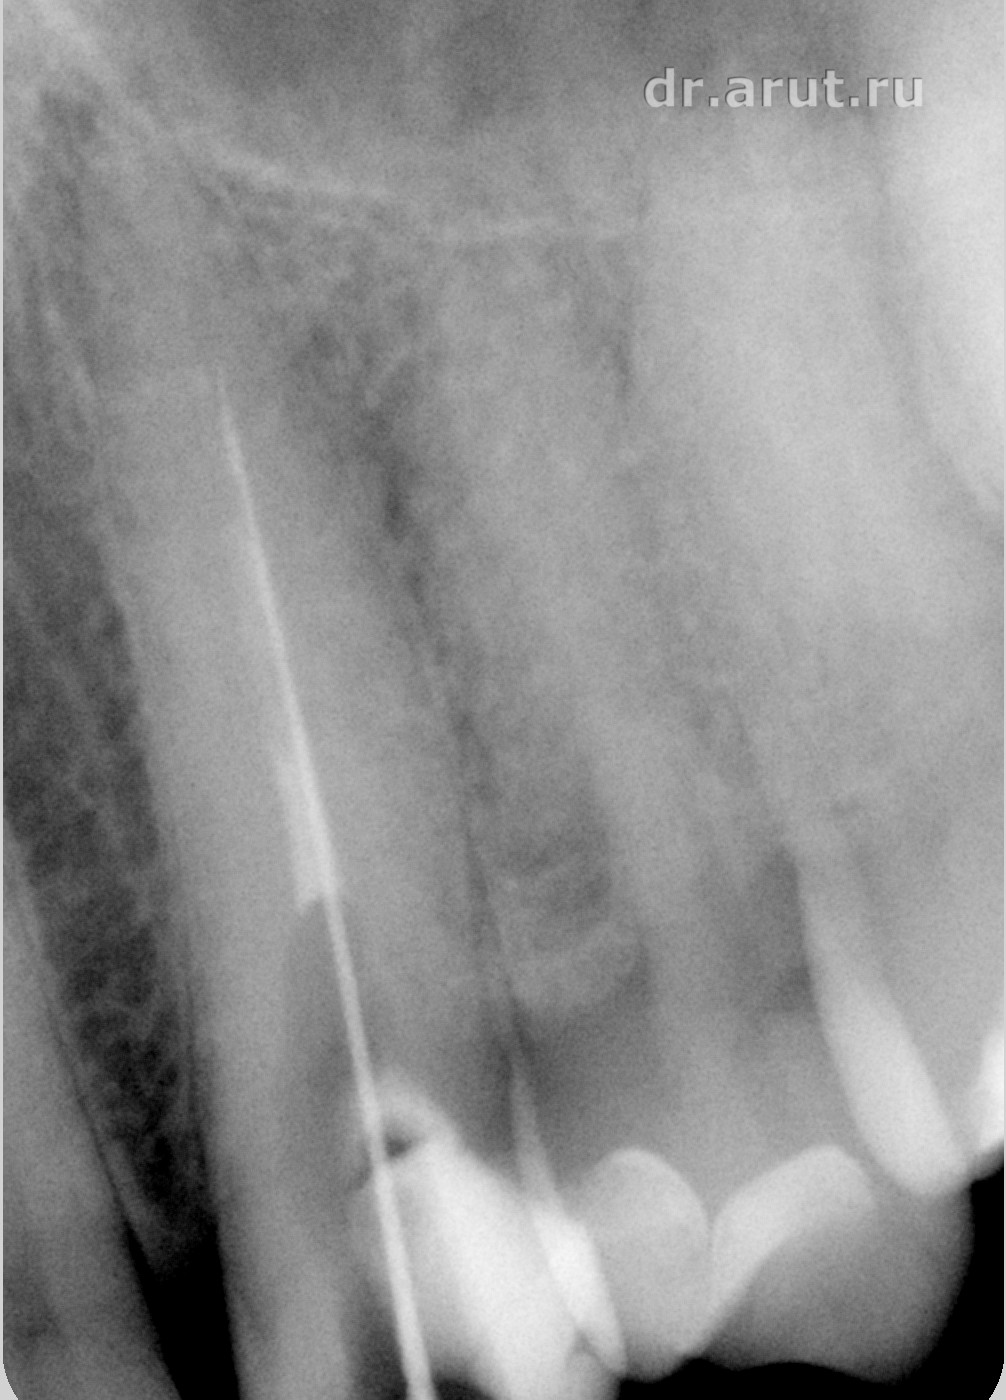

Лечение: После удаления пломбы был обнаружен титановый штифт, который после продолжительных усилий был извлечён, и благодаря этому создан доступ к корневому каналу. Во время распломбирования корневого канала по ходу пломбировочного материала (так как он является ориентиром), оказалось что канал далее непроходим. Проведя Rg-графию 23 зуба вместе с эндодонтическим инструментов выяснили, что в корне 23 зуба создан ложный канал и дальнейшая попытка его прохождения приведёт к перфорации корня. Около верхушки эндодонтического инструмента всё ещё оставалось небольшое количество пломбировочного материала, и было принято решение не продолжать распломбировывать и соответственно оставить его в ложном канале.

Спустя 5 лет сложно уже сказать когда был создан ложный канал — во время последнего лечения, т.е. 5 лет назад, или предпоследнего лечения. Возможно что его не 2 раза лечили, а лечили большее число раз. Сейчас уже это не важно, главное суметь его распломбировать до верхушки.

- Прохождение канала на всю длину